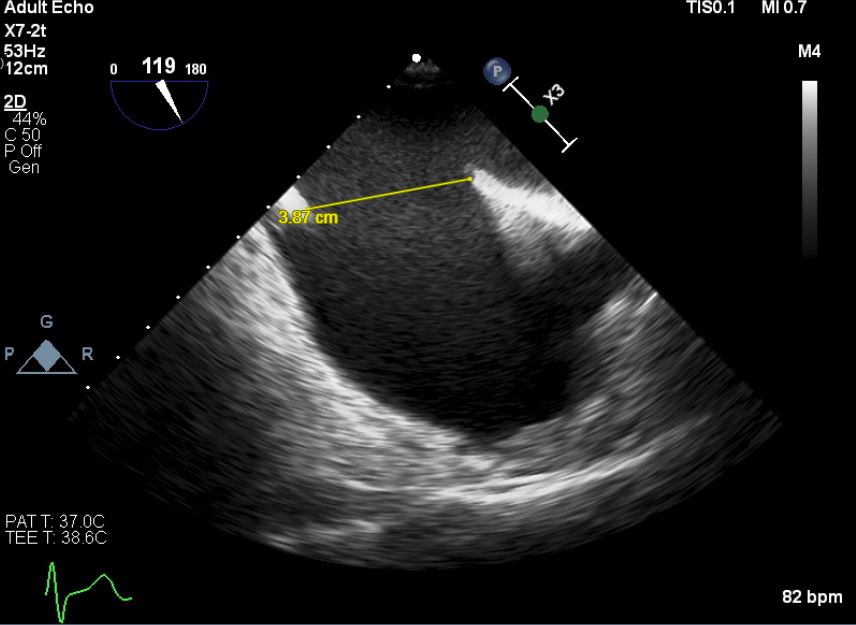

First, a trans-thoracic echocardiography(TTE) was done, there is a defect over the intra-atrial septum (IAS) with a dilated right heart. The doppler study exhibited a left to right shunting. A trans-oesophageal echocardiography (TOE) was done to assess the IAS & he has a secundum atrial septal defect(ASD), with anterior wall deficits but preserved inferoposterior wall length, largest diameter measuring 38.7mm. Estimated pulmonary arterial systolic pressure was 17 + 3 mmHG.

A right heart catheterisation was done, With Fick’s method revealing the pulmonary vascular resistance 2.83 wood unit indicating the need for ASD’s closure. A significant discrepancy arose in determining the true diameter of the ASD. In contrary to previous echocardiography, a repeated peri-procedural TTE measured it at 32mm with balloon inflation to occlude the defect. A decision was made to use a size 36mm occluder.